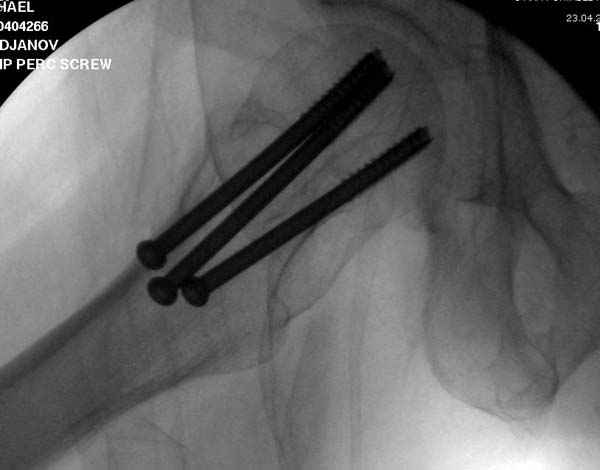

На второй день после выписки упал дома. Снимки приложены. Коллеги рекомендуют удаление шурупа и вытяжение. Что делать?

Привет из солнечного Будапешта с Eurotrauma-2008. Да, замечательный пример. Получается, профилактику расхождения отломков шейки надо было проводить каким-то реконструкционным или проксимальным гвоздем, причем сразу длинной версией. Сейчас, наверно, так и надо бы сделать.

Убрать винты, каким-то джойстиком в вертельной области сделать репозицию шейки, фиксировать ее спицами, а дальше вправлять и фиксировать как вертельный перелом.

Решайте проблемы по мере поступления. На первом этапе решение одно, и на мой взгляд верное. Ситуация изменилась кардинально - другое решение. Я бы избрал ресинтез, убрав винты заменил на Гамму. Что с ним будет послезавтра? - Будем решать послезавтра. Такая наша доля.

Правильно, ситуация изменилась, как говорят у нас теперь "different animal", надо решать проблему подвертельного перелома. При наличии различных вариантов фиксаторов, включая Страйкер Гамма 3, мы выбрали DePuy Antegrade Trachanteric Nail из-за многовариантности проксимальной фиксации и двойного изгиба. Вводится через вертел под 8 градусным углом, и есть достаточный передний диафизарный изгиб, предупреждающий пенетрацию дистального переднего кортекса.

Но ведь и головка бедра сползла в варус - отчего ограничились только фиксацией подвертельного перелома, а не убрали винты и не сделали репозицию шейки?